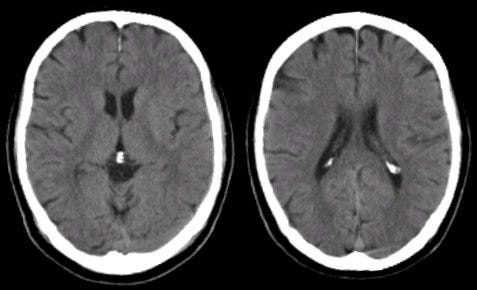

The downside is radiation. This is a risk if you get too much of it. The upside is now health professionals can see what’s going on inside you, and if it’s a big deal like bleeding, act faster. Bleeding shows up really well because it’s dense, and thus bright white on the scan. Bone fractures are also well visualized. Bone also is bright white, but not looking like a regular unbroken bone, you get the idea.

The resolution isn’t that good. It’s good for things that need to be done fast, or cheap, or especially, both. It’s almost useless for imaging the brain, unless we’re trying to see if there’s bleeding, or midline shift, or something really obvious. If there’s bleeding, it’s awesome.

If you need to look fast, because you’re worried someone had a stroke and it might be hemorrhagic, which means bleeding, a computed tomography scan will save your life. It’s good at big obvious life-threatening changes, and it’s fast, so we can do it easily in the ER.

It also has a role in acute stroke, again because of the speed of the scan, and the ability to do some fancy math when it comes to perfusion of the brain with blood, if we suspected stroke. When every minute counts, the CT scan is where it’s at. If you add contrast— more dense stuff to increase the ability to catch x-rays in soft tissue— it can do other things like pick up blood clots in the lungs, or problems in your abdomen.